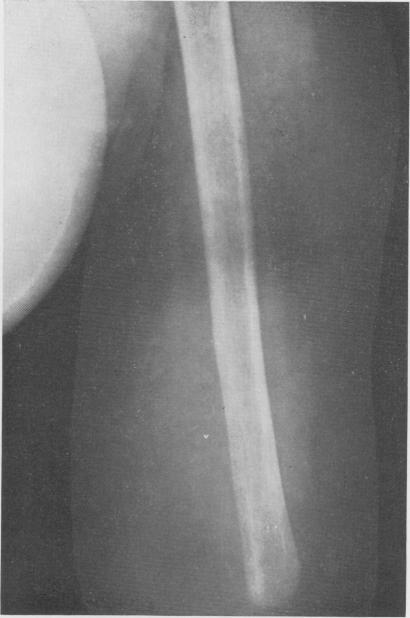

Chemotherapy of cancer: regional perfusion utilizing an extracorporeal circuit.

Ann Surg. 1958 Oct;148(4):616-32. doi: 10.1097/00000658-195810000-00009.